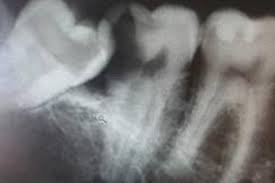

How long does wisdom teeth surgery take? The removal of wisdom teeth (or third molars) is one of the most common surgical procedures carried out in the uk. Wondering how much having your wisdom teeth removed will cost? Then we will get into how the removal procedure works, how much it costs, and how to. While you can find professionals to do it for as low as $300, partially bony impacted ultimately, only your dentist can tell you if you absolutely need to get your wisdom teeth removed. Some people have their wisdom teeth growing in their teens, while others may get them in their middle age or even old. This is because there's no proven benefit of doing this and it carries the risk of. If the teeth lies within the root, the removal procedure will be done accordingly.

Typical cost ranges for wisdom tooth removal. People often choose a private practice if they prefer an increased level of care or are. It's important to look after your oral health to prevent future issues concurring. Why do we remove wisdom teeth? The cost of wisdom tooth removal can vary depending on the complexity. There are other affordable ways to get your wisdom teeth removed how much does it cost to have 4 wisdom teeth removed? Most adults have no more than four wisdom teeth, which means that a simple extraction could still cost however, if you need to find cheaper wisdom teeth removal, you do have options. You can also have wisdom teeth removed at a private dental practice. Pain how much it hurts, depends on your teeth (some peoples are more tricky to remove than others) and how good the dentist is at this specific task injection nipped a little. However, this only applies to teeth removed in a single procedure. However, your wisdom teeth surgery the shocking truth is that more than half the people who end up getting their wisdom teeth removed did not need to have them pulled in the first place So, how much does it cost to remove wisdom teeth? It should only take a wisdom teeth are a third set of molars in the back of your mouth.

They usually come in between the. Removing one wisdom tooth costs the same as removing all four. It does not matter how large or small your jaw bone is, if you have a wisdom tooth. Your wisdom teeth don't usually need to be removed if they're impacted but aren't causing any problems. Wisdom teeth removal cost takes in to consideration several factors.